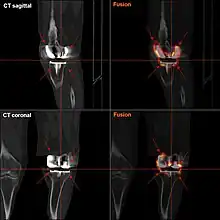

FDG-PET CT showing septic loosening of knee prothesis; the FDG-enrichment shows entensive inflammatory foci: demonstrative: the PET-image is, unlike a CT reconstruction, not disturbed by the high radiation attenuation of the prothesis.